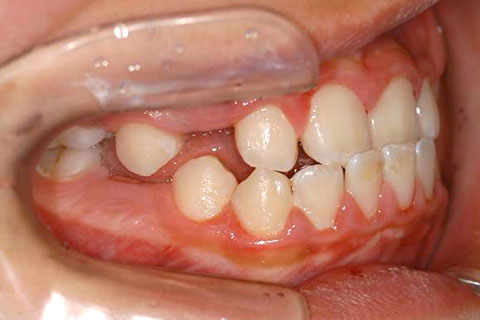

下あごが上あごより突出しているか、上あごが下あごより後退している状態で、咬み合わせが逆になっているので反対咬合ともいいます。お子様の場合、受け口(反対咬合)を放置していると、成長期において下あごが過大に成長し悪化しますので、出来る限り早い時期に治療することをおすすめします。受け口(反対咬合)は見た目の問題だけでなく顎の動きを制限し、将来的に顎の痛み(顎関節症)を引き起こす場合があります。また、お子様の場合は、正常な上顎の成長を阻害する可能性があります。

受け口(反対咬合)の症例

症例一覧